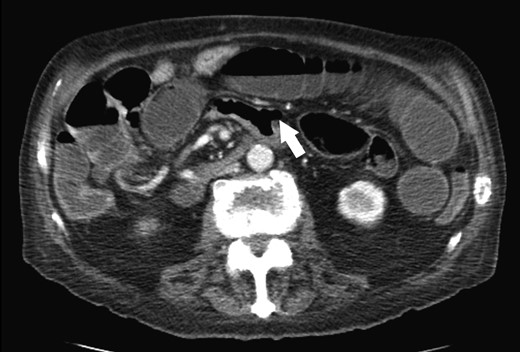

An 86-year-old male previously treated for hypertension presented to the emergency department with two days of sudden abdominal pain and nausea which resolved temporarily after self-induced emesis. Patient was examined and investigated thoroughly. Temperature was 36.3 C, blood pressure was 138/81, and pulse was 78. Physical examination revealed a tender, firm and distended abdomen with hyperactive sounds. Laboratory analysis revealed hemoglobin at 10.3 g/dL, leukocytes 3.1 K/cmm, urea nitrogen 19 mg/dl, creatinine 0.6 mg/dl, sodium 137 mmol/l, potassium 3.6 mmol/l, chloride 104 mmol/l, bicarbonate 24 mmol/l, calcium 8.6 mg/dl, total protein 6.3 g/dl, albumin 3.1 g/dl, total bilirubin 0.7 mg/dl, alkaline phosphatase 98 U/l, SGOT 20 U/l, SGPT 27 U/l. Laboratory values were consistent with patient’s previous clinic visits. Computed tomography (CT) of the abdomen revealed a fluid-filled, significantly dilated stomach as well as multiple dilated loops of small bowel with air-fluid levels consistent with mechanical small bowel obstruction caused by intussusception of small bowel (Fig. 1). After initial fluid resuscitation and antibiotic administration, consent was obtained for emergent exploratory laparotomy. The exploratory laparotomy revealed a 3.0 × 2.5 cm intraluminal calculus in the ileum responsible for the small bowel obstruction, without evidence of intussusception (Fig. 2). The obstructing enterolith was ‘milked’ proximally until it reached, and subsequently ‘fell into,’ an isolated 6.0 × 3.0 cm jejunal diverticulum which had not been previously noted on CT imaging. The enterolith was removed along with the segment of the jejunum containing the isolated diverticulum, which was the source of the enterolith (Fig. 3). On histologic examination, the mucosa of the extracted diverticulum was found to be granular and erythematous; the remaining small bowel had marked mucosal ulceration and near-transmural inflammation with granulation tissue. Hospital course was complicated by decreased urine output that resolved after fluid resuscitation. On the fourth postoperative day, nasogastric tube was discontinued, diet was advanced and tolerated, and the patient was discharged. Review of the patient’s CT scan of the abdomen revealed the isolated jejunal diverticulum that was consistent with the excised diverticulum (Fig. 4).

Jejunal diverticulosis complicated by enterolith formation is rare. Enteroliths are classified as primary or secondary. Primary stones are formed within the intestine, while secondary stones are introduced from outside the gastrointestinal tract such as the gallbladder or kidney [7]. True primary stones can be formed de novo from bile precipitation that occurs due to pH changes and dyskinesia that occurs within the diverticula; false primary stones can form as a result of undigested food entrapped within the diverticula [7, 8]. Once stones are formed, they can dislodge from diverticula into the intestine and cause obstruction. Most cases of small bowel obstruction due to enterolith are not associated with concurrent diverticulitis. Small bowel obstruction due to enterolith associated with jejunal diverticulitis have been previously described, however the patients presented in these reports had diffuse jejunoileal diverticulosis, or presented with multiple jejunal diverticula [8, 9]. The case presented occurred in a patient from the Navajo Nation of Northeastern Arizona. To our knowledge, only one case of small bowel obstruction by enterolith associated with diverticulitis of a single jejunal diverticulum has been previously documented in Europe [10]. We present this case as the first to be documented in the United States and hope it serves as additional evidence that a single jejunal diverticulum, not just diffuse jejunoileal diverticulosis, may lead to enterolith formation and subsequent small bowel obstruction, and therefore, should be included in the differential of cases of acute abdomen. We also present this case due to the peculiarity of being readily misdiagnosed as intussusception with a prominent ‘target’ sign and the ease by which isolated jejunal diverticula may be missed on initial reading of imaging. Cases of intussusception secondary to enterolith formation in JD have been described in literature, so an additional consideration of this case could be that intussusception may have been present at time of imaging that could have resolved by the time of exploratory laparotomy, however, we did not find edema or signs of compromise in the intestine adjacent to the obstruction that would indicate that the enterolith acted as a lead-point for intussusception. Additionally, we recommend that gallbladder, kidneys, and ureters are inspected, as these could be rare sources of small bowel obstruction that have been previously documented in literature as well.